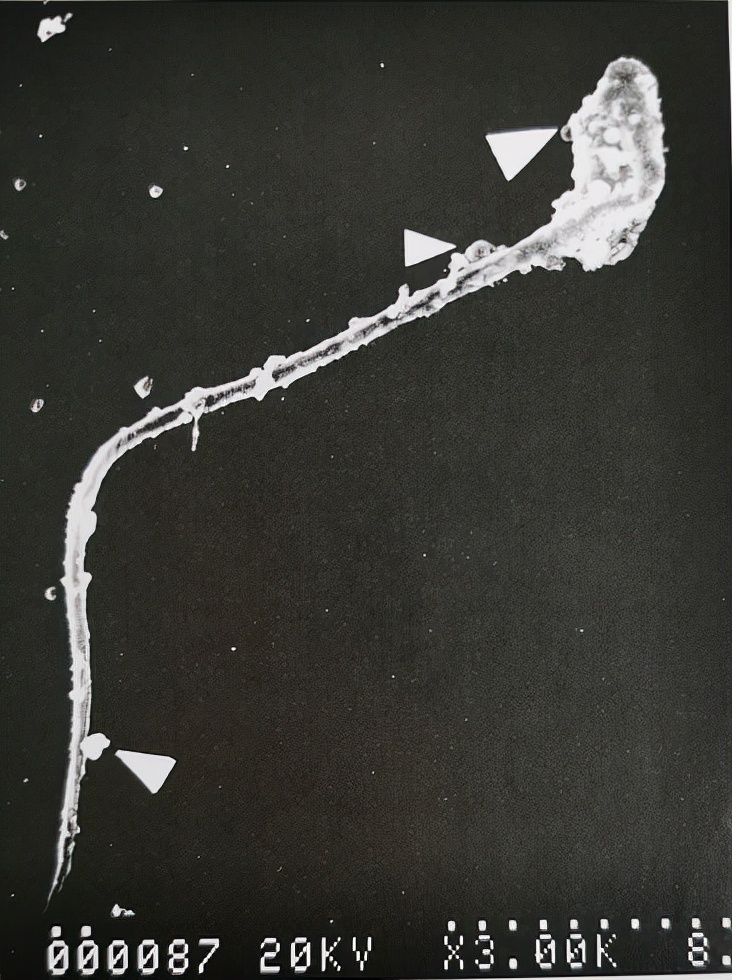

扫描电镜下观察的被UU感染的精子

uu感染是什么意思,uu感染严重吗